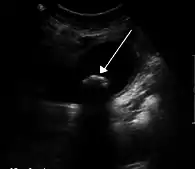

|   La colique hépatique est souvent liée à des calculs biliaires | |

On retrouve ce symptôme, par exemple, lors de l'expulsion d'un calcul hors de la vésicule biliaire (en même temps que la bile), lors de la contraction de celle-ci. Le calcul provoque une douleur vive en se déplaçant dans les voies biliaires : cette douleur peut irradier jusqu'aux côtes et l'épaule du côté droit.